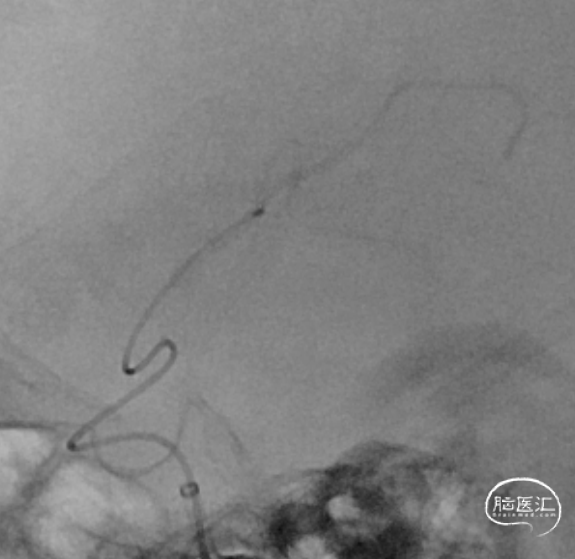

沿微导管送入4.0*30mm Syphonet®取栓支架,造影显示:造影见左侧大脑中动脉M1段约1.8cm细长狭窄显影。大脑中动脉一干仍不显影,考虑狭窄明显并血栓形成。以静脉替罗非班推注12ml,同时静脉7ml/h维持。

沿4.0*30mm Syphonet®取栓支架输送导丝送入2.0*15mm SacSpeed®球囊扩张导管,于大脑中动脉狭窄段缓慢扩张成型后,保留Syphonet®取栓支架造影后提示远端血流改善。5分钟后支架锚定、负压下将6F Tethys®中间导引导管拟送至支架近端并接触血栓(中间导管无法到位),用50ml注射器保持抽吸管负压,回拉Syphonet®取栓支架,取出1枚2.0*2mm细小血栓。